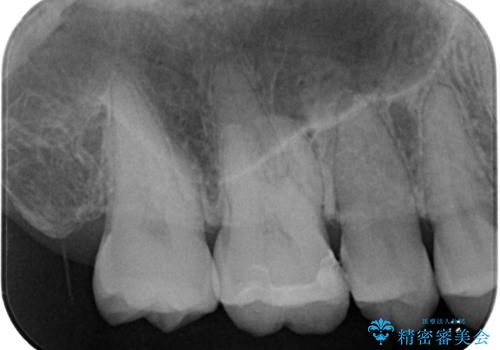

- 銀歯をやり替えたいとのことで来院された患者様です。金属の詰め物の大きさ、虫歯の範囲を考慮してセラミックの詰め物(セラミックインレー)で治療を行っていくことにしました。

拡大鏡視野下で、金属の詰め物(メタルインレー)、虫歯の除去を行い、セラミックインレーに適した形に整えました。

歯と歯の間の虫歯をコンポジットレジンや保険のメタルインレーで治すと段差ができたりして清掃性が悪くなるので、セラミックインレー修復やゴールドインレー修復などの適合の良い詰め物で治療することをオススメします。